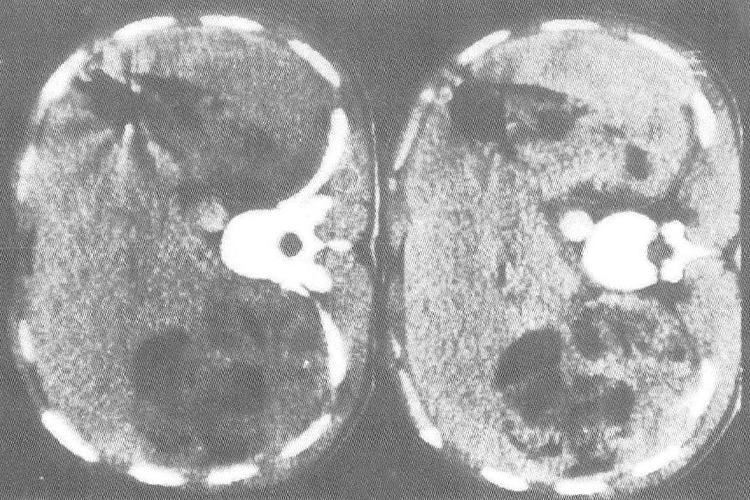

血管平滑肌瘤影像学可见不规则形或椭圆形,内部呈混合回声,分布不均匀,以低回声为主,部分接近无回声,肿块内部有散在分布的数个强回声斑伴浅声影,肿块后方回声增强,境界欠清晰,包膜回声带不明显。